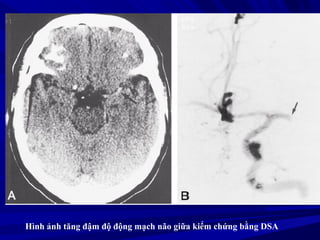

Hình ảnh tăng đậm độ động mạch não giữa kiểm chứng bằng DSA

Giai ñoaïn toáicaáp (< 6 giôø) - Bình thöôøng (50-60%) - Daáu taêng ñaäm ñoä ñoäng maïch 25-50 % - Giaûm ñaäm ñoä nhaân ñaäu HÌNH AÛNH CT ÑOÄT QUÎ TMNCBC

Hình ảnh tăngđậm độ động mạch não giữa kiểm chứng bằng DSA